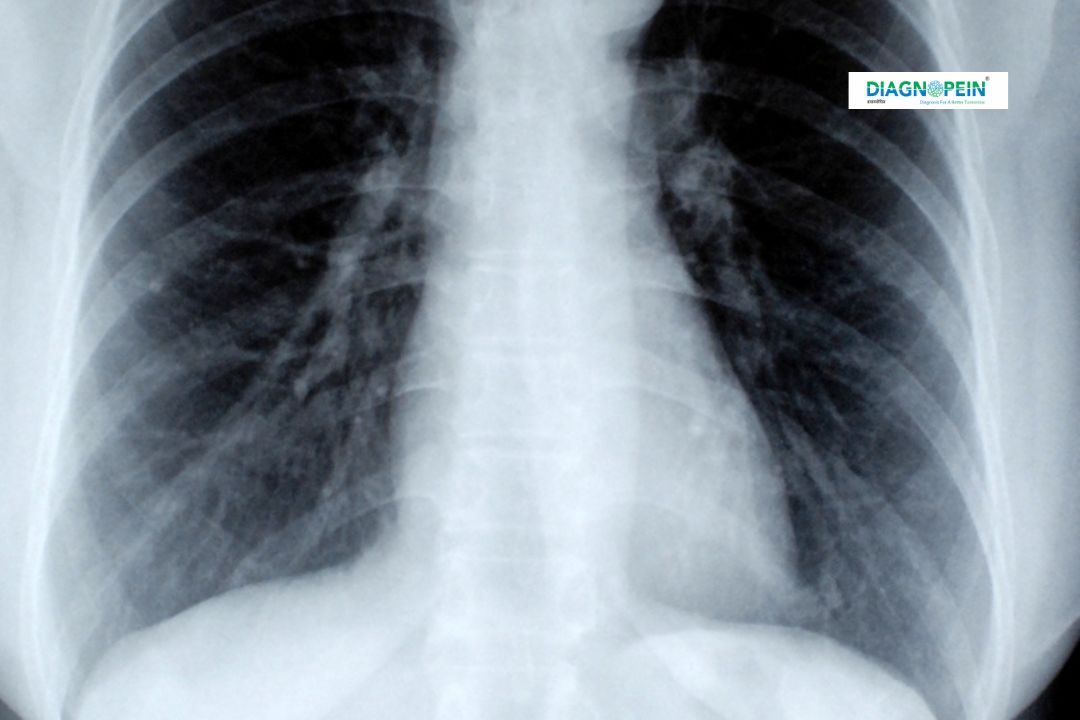

The X-Ray L.S. Spine Lateral is a specialized X-ray view taken from the side of the lumbar spine. It helps visualize each vertebra, intervertebral disc space, and spinal curvature. This imaging is commonly used to evaluate chronic back pain, injuries, or post-surgical healing. At Diagnopein in karad, our radiology experts use advanced digital machines for sharper images and minimal radiation exposure.

This test helps identify several spinal issues such as scoliosis, spondylolisthesis, degenerative disc disease, and traumatic fractures, allowing healthcare professionals to make accurate treatment plans.